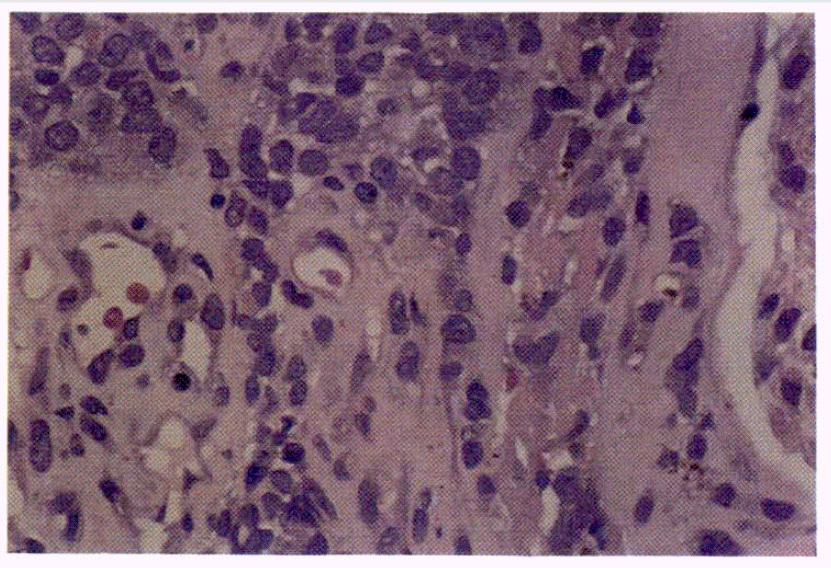

In February, 1986 she had been diagnosed as stage I malignant melanoma of the left cervical region which was treated with wide excision and left radical neck dissection. The pathologic report revealed it to be Clark’s level IV and 5 mm in thickness (Fig. 1). Since then she had been followed regularly through the outpatient department without any evidence of recurrence.